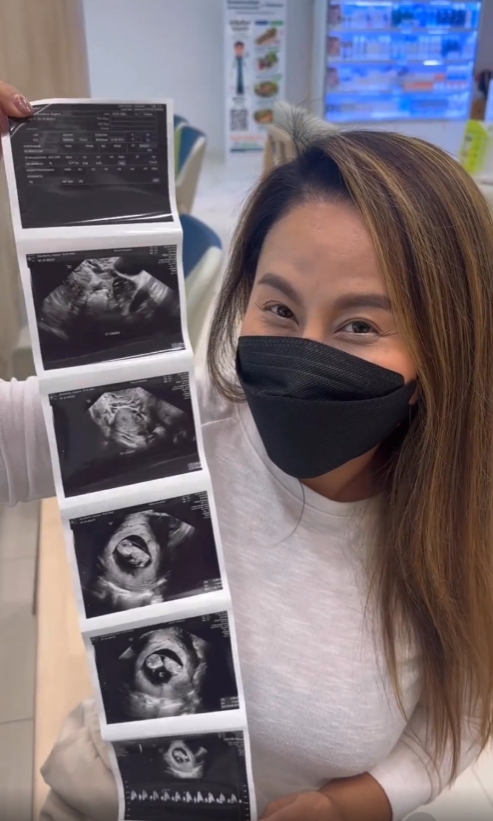

“ลาล่า อาร์สยาม” โชว์ผลอัลตาร์ซาวน์ ประกาศข่าวดี “น้องสาว” ท้องลูกคนที่สองแล้ว

ทำเอาคนในครอบครัวดีใจกันสุดๆ จนน้ำตาไหลกันเลยทีดียว สำหรับ “ลาล่า ขวัญนภา เรืองศรี” หรือ “ลาล่า อาร์สยาม” หลังเจ้าตัวได้โพสต์คลิปโชว์ภาพผลอัลตร้าซาวด์ พร้อมประกาศข่าวดี น้องสาวของเธอที่แต่งงานกับสามีชาวฝรั่งเศส ได้ตั้งท้องลูกคนที่สองแล้ว โดยระบุข้อความว่า..

“ท้องแล้ว..เย้ๆๆ รอมานาน ฝรั่งเศสน้อยมาแล้ว หลานคนที่ 2 ดีใจที่สุดในชีวิต ชาตินี้ก็คุ้มค่าที่สุดแล้ว น้ำตาแห่งความสุข ขอต้อนรับสมาชิกตัวน้อยอีกคนนะลูก ขอให้หนูแข็งแรง อีก 5 เดือนเจอกันนะลูก เย้ๆๆๆ”